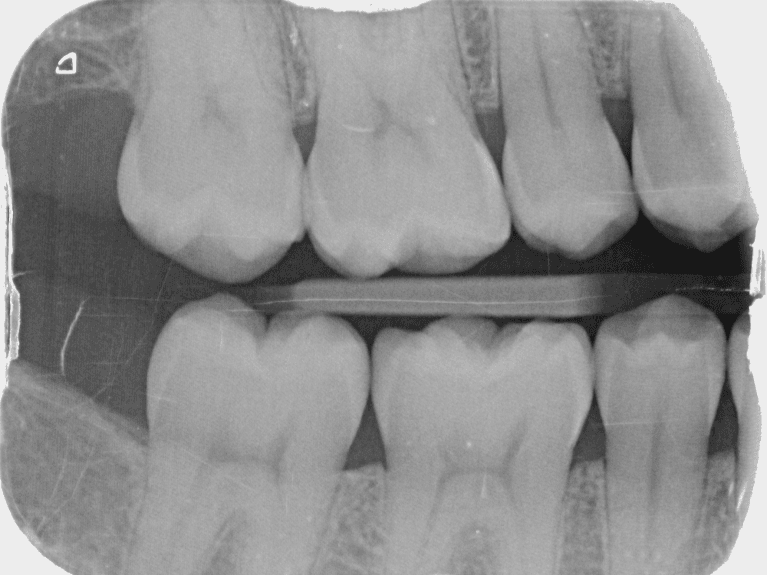

Digital X-Rays

Your Lower Templestowe dentist relies on dental x-rays to evaluate your oral health. We use digital x-rays because this technology exposes patients and staff to less radiation than traditional films.

Digital x-rays are also easy to store electronically and better for the environment because they do not require chemicals or disposal.

Another important benefit is that there is no waiting around for films to be developed. In fact, it takes only a few seconds for clear images to be ready for viewing.